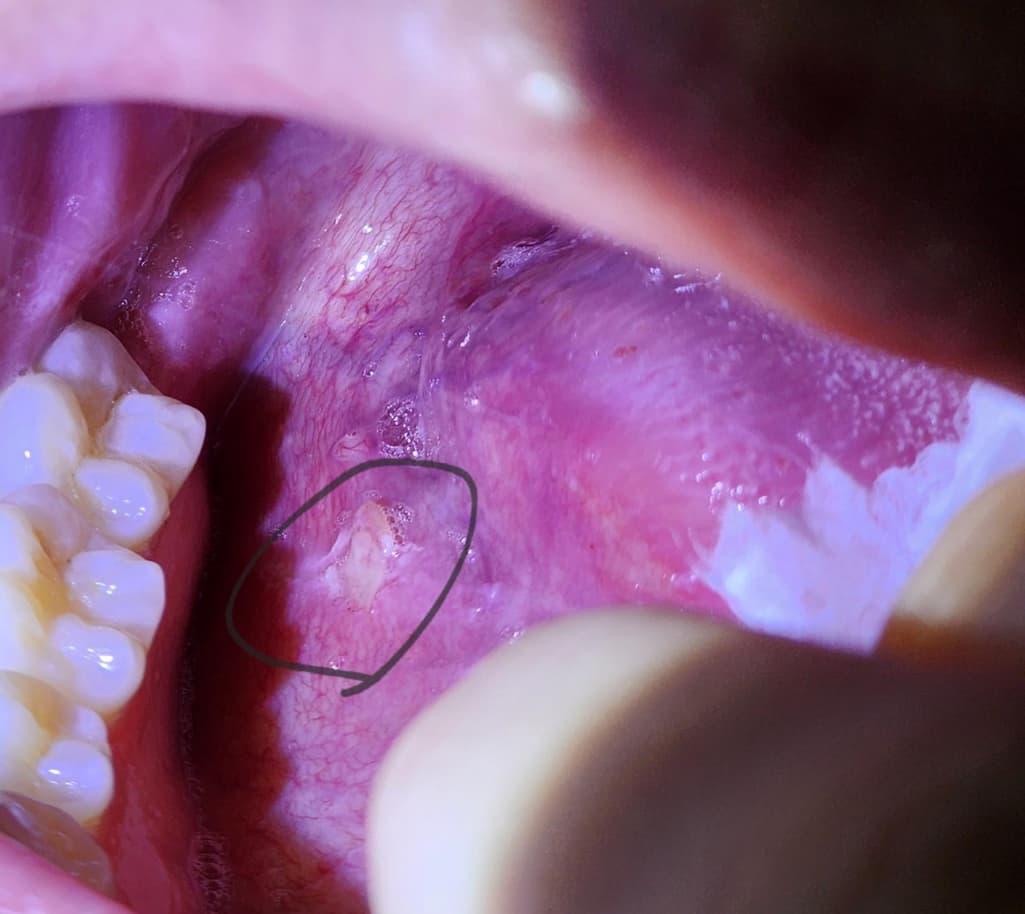

이거 혀에 뭐가 났는데 구강암 일까요?

한 10일 정도 된거 같아요. 오른쪽 혀 옆면 약간 아래 부분에 이렇게 있는데 가만히 있으면 괜찮은데 음식 먹을때 좀 아프네요.. 가만히 있으면 괜찮아질까요?

구강암은 아니고 혀가 자극을 받아서 혓반들이 생긴거 같습니다. 큰 문제가 잇는건 아니니 너무 걱정하지마세요.

사진으로만 봤을 경우에는 점막에 자극으로 인해서 손상이 된것으로 보입니다. 구강 점막은 치유가 잘 되는 조직이기 때문에 해당 부위를 자극하지 않는다면 보통 이 주 정도 지나면 아물게 됩니다. 정확한 확인을 위해서 치과에서 진료를 받아보는 것을 권해드립니다.

구강암보다는 구내염일 가능성이 더 높아보이며 구내염은 보통 2주일 이내에는 사라집니다.